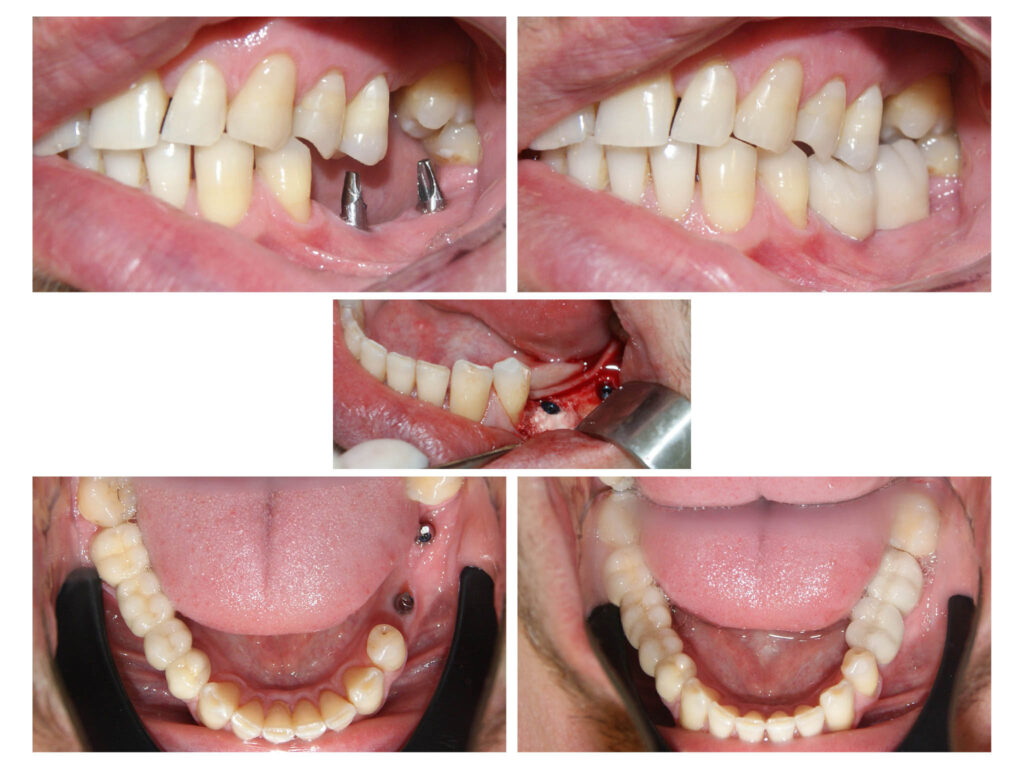

Aplicare implante dentare cu usoara adiție de os artificial si protezarea lor